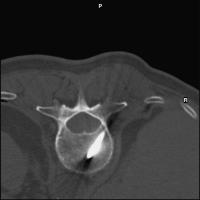

Vertebroplastie - Wirbelkörperpunktion

Abbildung 2: Interkostovertebraler Zugangsweg.

Keywords:

Brustwirbelsäule

,

interkostovertebral

Mineralstoffwechsel

Röntgenbild

Wirbelkörperpunktion